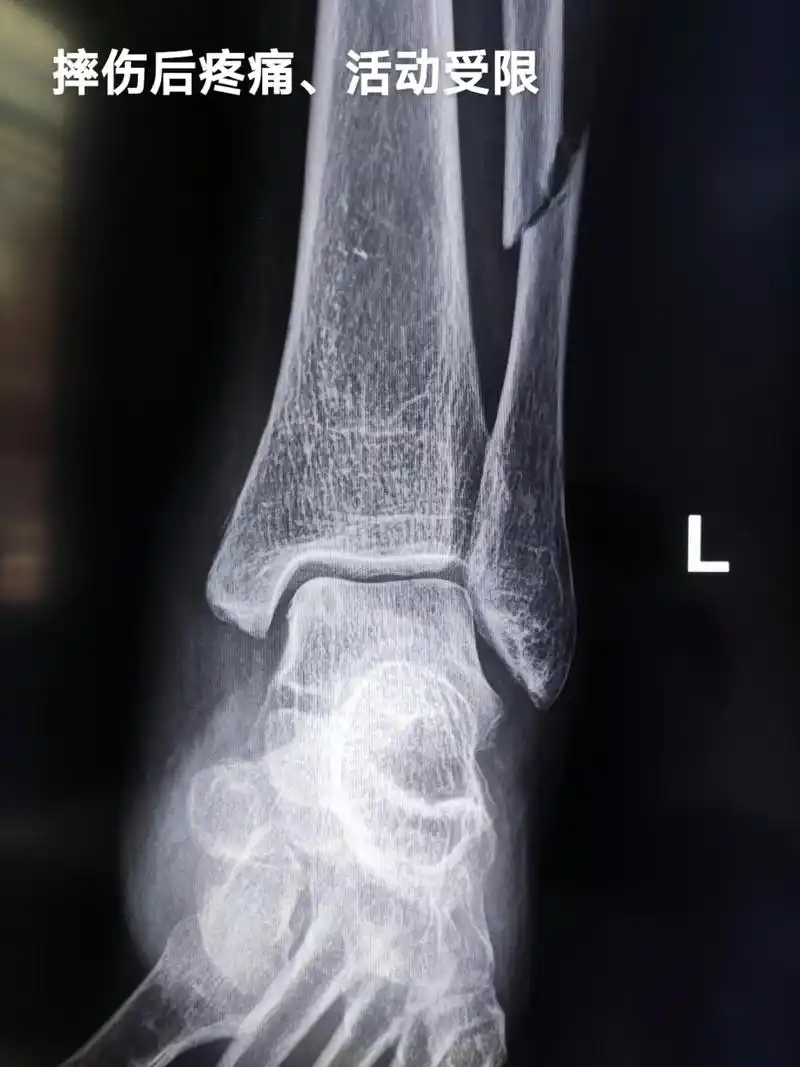

谁来试试,这个骨折怎么治? [病例帖]

医学影像 摔伤致左小腿下段疼痛,活动受限,x线见腓骨骨折, - 抖音

一例胫腓骨骨折

外踝骨裂